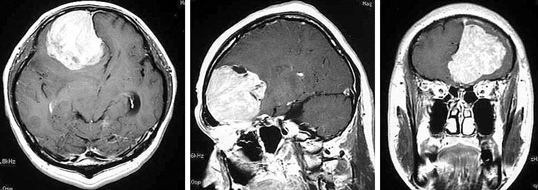

48歳男性。

いつも頭痛がしていた、最近仕事の能率が悪くなったという訴えがあります。MRIで脳腫瘍と診断しました、大きな髄膜腫といわれる主要です。髄膜腫はゆっくりと大きくなる良性脳腫瘍です。前頭部にできると認知症様症状を出すことが多いことが知られています。開頭術により全摘出することができました。